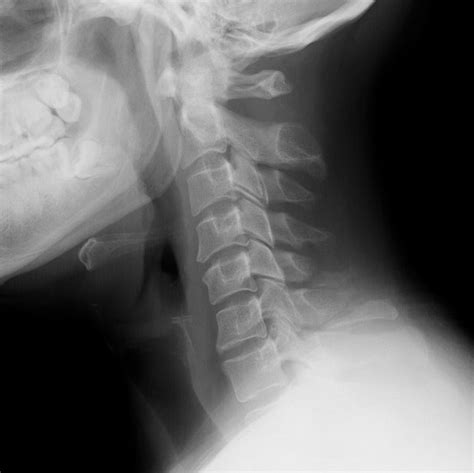

Diagnosis of Clay Shoveler's Fracture

Diagnosing a Clay Shoveler's Fracture involves a combination of physical examination and imaging tests. The diagnostic process typically includes:

• Imaging Tests:

• X-rays: To visualize the fracture and assess the extent of the injury.